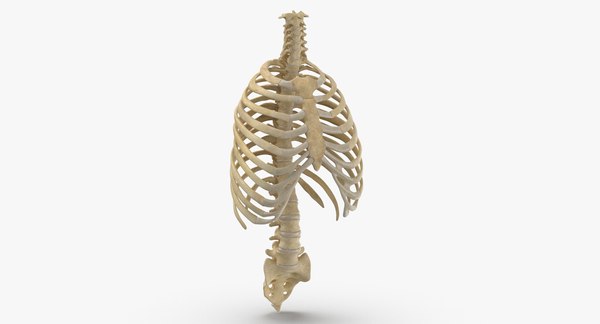

늑골이라고 명명되며 12쌍을 이루고 있는 갈비뼈는 내부의 심장, 폐, 간 등 주요 장기를 막아주는 역할은 물론 몸의 형태를 계속하고 정상적인 생활을 하는 데 있어 굉장히 귀중한 인체 부위에 부합됩니다.